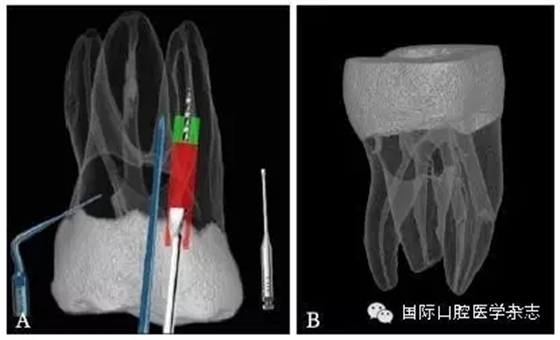

3.2.1 牙本質(zhì)厚度評估 取出分離器械需要損失部分牙本質(zhì),牙本質(zhì)的損失量包括縱向損失和橫向損失。縱向損失決定于取出時分離器械冠方末端需要暴露的長度,橫向損失決定于分離器械的斷端直徑以及選用取出器械的方法(如超聲法或是環(huán)鉆法等)。牙本質(zhì)損失量過多會導(dǎo)致根管穿孔、根管折斷等并發(fā)癥[7](圖3)。

A:紅色及綠色的部分分別表示用改良GG鉆及超聲工作尖去除牙本質(zhì)的量;B:MicroCT掃描圖像顯示取出下頜第一磨牙近頰根管中分離器械后,導(dǎo)致了根管穿孔。

圖 3 取分離器械過程中會導(dǎo)致牙本質(zhì)損失,甚至穿孔等并發(fā)癥

取出分離器械后,根管壁的殘余牙本質(zhì)厚度是影響牙根抵抗力的重要因素,因而,可以認(rèn)為殘余牙本質(zhì)的厚度是影響分離器械取出與否的最重要的因素之一[8]。

目前,對于分離器械周圍牙本質(zhì)厚度的評估以及取出后殘余牙本質(zhì)厚度的預(yù)測主要需借助影像學(xué)檢查,例如根尖片、錐形束CT(cone beamcomputed tomography,CBCT)圖像等。傳統(tǒng)的平行投照的根尖片無法反映三維立體結(jié)構(gòu),且往往存在解剖結(jié)構(gòu)影像的重疊,不利于臨床判斷,具有一定的局限性。多位學(xué)者[10]的研究表明:平行投照的根尖片會高估實(shí)際的牙本質(zhì)壁的厚度。一些學(xué)者[11-12]的研究表明:當(dāng)分離器械位于上頜第一磨牙近中根管時,采用成角投照(21°)的拍攝技術(shù)與平行投照技術(shù)得到的X線片相比,能更準(zhǔn)確地評估牙本質(zhì)的厚度,為分離器械取出與否提供指導(dǎo)(圖4)。近年來,CBCT在牙髓病學(xué)中的應(yīng)用越來越廣泛,由于CBCT能清楚地反映牙及牙根周圍組織的三維立體結(jié)構(gòu),為牙本質(zhì)厚度的評估與預(yù)測提供了可行性(圖5);因此,CBCT在器械分離的病例術(shù)前風(fēng)險評估方面具有較好的應(yīng)用前景。

圖 5 使用CBCT評估分離器械周圍牙本質(zhì)厚度